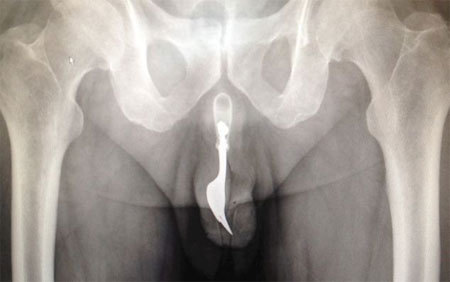

Các bác sĩ ở Australia đã phải can thiệp để lấy ra ngoài một chiếc dĩa thép dài 10cm, bị mắc kẹt bên trong "cậu nhỏ" của một cụ ông 70 tuổi.

Giới truyền thông địa phương đưa tin, cụ ông 70 tuổi đã được đưa vào khoa cấp cứu của Bệnh viện Canberra, Australia trong tình trạng chảy máu dương vật. Ông sau đó thú nhận đã nhét chiếc dĩa vào đường niệu đạo của mình nhằm thủ dâm.

Theo báo The International Journal of Surgery, chiếc dĩa cắm ngập sâu bên trong cơ thể bệnh nhân đến mức các bác sĩ ban đầu không biết nguyên nhân khiến ông đau đớn. Tuy nhiên, sau khi được tiết lộ căn nguyên sự việc và xác định được vị trí của "thủ phạm", họ đã tiến hành nhiều thủ thuật trích lấy chiếc dĩa ra ngoài bằng kìm kéo và chất bôi trơn.

Quá trình đã diễn ra thành công. Nười đàn ông lớn tuổi rốt cuộc đã xuất viện về nhà và không phải hứng chịu bất kỳ tổn thương lâu dài nào.